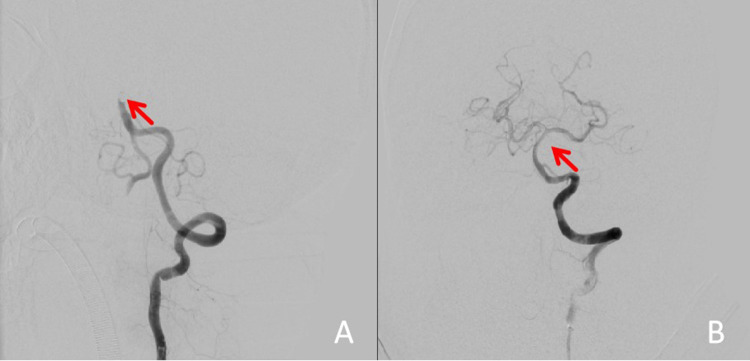

急性椎基底动脉闭塞(AVBAO)仅占缺血性卒中的1-2%,但致残率和死亡率高。机械取栓联合静脉溶栓可快速实现血管再通,显著改善患者预后。本报告描述一名73岁男性因AVBAO昏迷入院。MT后,基底动脉再通成功;然而,患者随后发展为罕见但严重的双侧动眼神经麻痹并发症。该报告强调需要仔细的术前计划,包括血管解剖和血栓特征的详细评估,以及操作人员专业知识的重要性。改进术中技术和密切的术后监测可能有助于预防并发症,如血管损伤或栓塞复发。此外,临床医生应该意识到早期DWI(弥散加权成像)在检测脑干梗死方面的局限性,以及术后临床警惕的必要性。

Acute vertebrobasilar artery occlusion (AVBAO) accounts for only 1-2% of ischemic stroke, but it has high disability and mortality rates. Mechanical thrombectomy (MT) combined with intravenous thrombolysis can quickly achieve vascular recanalization and significantly improve patient prognosis. This report describes a 73-year-old male who was admitted to the hospital in a coma due to AVBAO. After MT, successful recanalization of the basilar artery was achieved; however, the patient subsequently developed the rare but serious complication of bilateral oculomotor nerve palsy. The report emphasizes the need for careful preoperative planning, including detailed assessment of vascular anatomy and thrombus characteristics, and the importance of operator expertise. Improved intraoperative technique and close postoperative monitoring may help prevent complications such as vessel injury or embolic recurrence. Additionally, clinicians should be aware of the limitations of early DWI (Diffusion-weighted imaging) in detecting brainstem infarcts and of the need for clinical vigilance in the postoperative period.